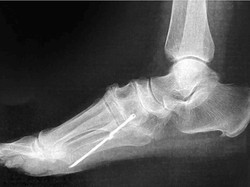

Awal Mula Dokter Temukan Besi Nancap di Dalam Kaki Pasien Setelah 40 Tahun

Dokter menemukan batang besi dalam kaki pasien seorang nenek. Batang besi tersebut baru ketahuan setelah 40 tahun bersarang di dalam kaki itu.